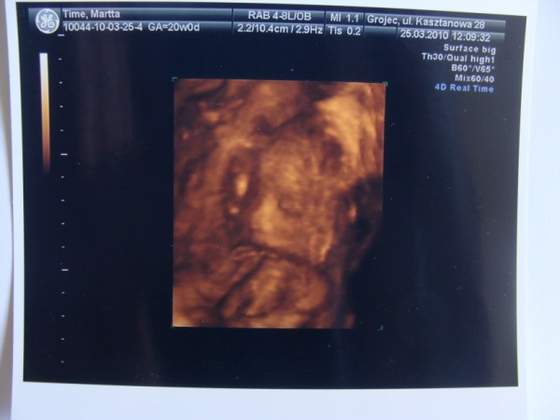

Oto mój Dzidziuś

Niestety nadal nie znam płci... Przykleił się do macicy i za nic nie chciał się pokazać, tylko kolanko co najwyżej i to dopiero pod koniec USG. Mam filmik ale coś mi się dzieje z internetem i nim wgram na youtube, to przerywa i taki finał. Zdjęcie mi dał tylko jedno, jestem w szoku z tą kością nosową)) 22 tygodnie 5 dni takie ma parametry, oby się z nosem nie wdało do Leszka

Leszek był ze mną na badaniu bo się zwolnił z pracy i trzymał mnie kurczowo za kolano a ja chociaż myślałam, że się tam poryczę to dostałam ataku śmiechu ze szczęścia i lekarz był lekko zdziwiony całą sytuacją, ale co tam